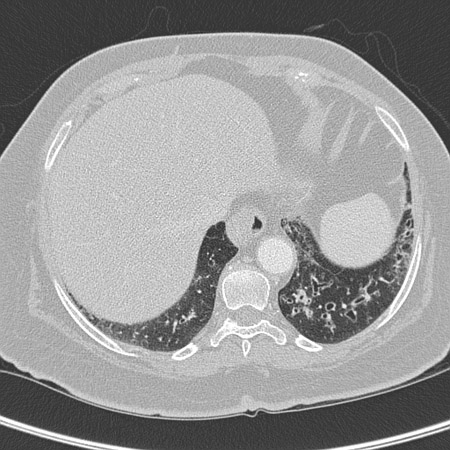

[Figure caption and citation for the preceding image starts]: Tomografia computadorizada (TC) do tórax com presença de anel de sinete à esquerda em paciente com bronquiectasiaDo acervo pessoal da Dra. S.M. Bhorade, University of Chicago Medical Center [Citation ends].

[Figure caption and citation for the preceding image starts]: Tomografia computadorizada (TC) do tórax com vias aéreas dilatadas e espessadas e um padrão de árvore em brotamento periférico em paciente com bronquiectasiaDo acervo pessoal da Dra. S.M. Bhorade, University of Chicago Medical Center; usado com permissão [Citation ends].